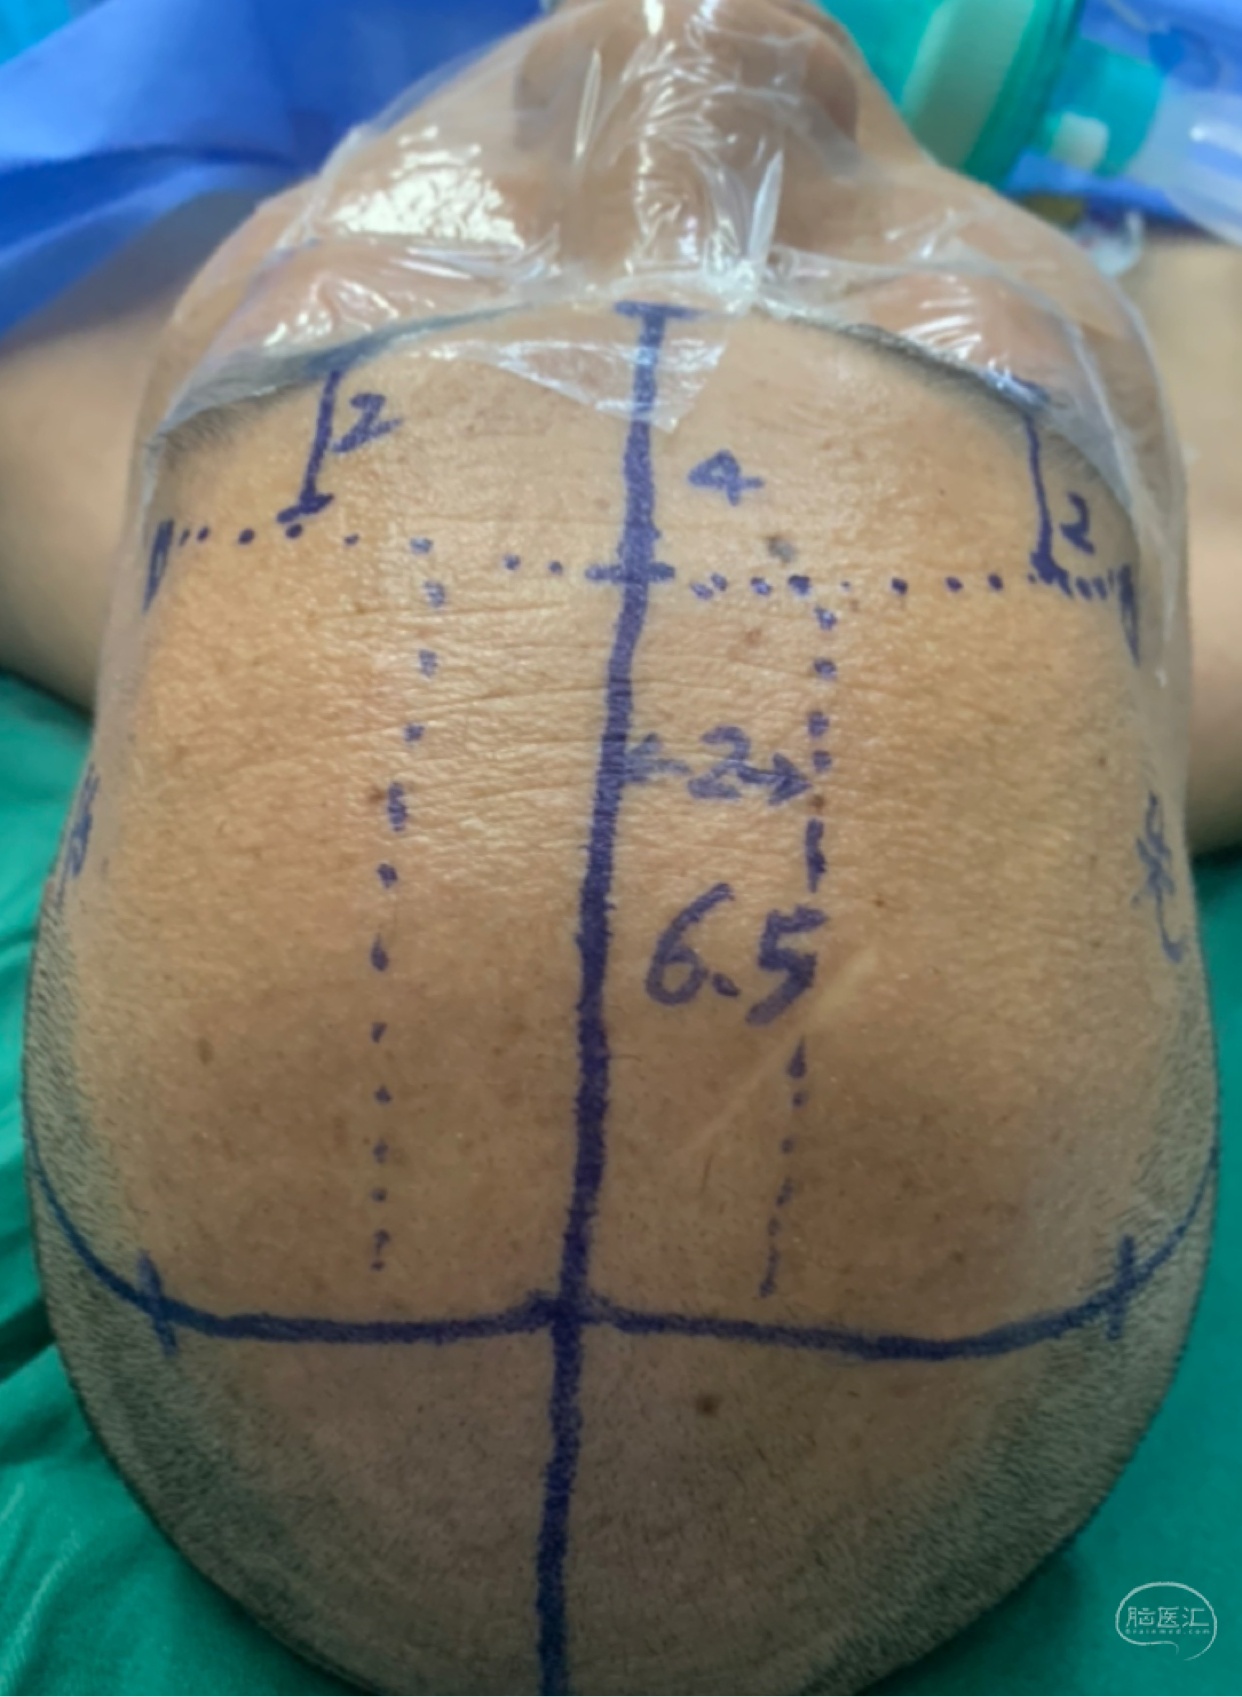

双侧入路计划(为降低优势半球损伤风险先右侧处理,实在不好搞再左侧)

从右额分块切除处理大部分后,因条件所限单侧入路风险高遂加开左侧额外侧(骨窗较右侧小)。